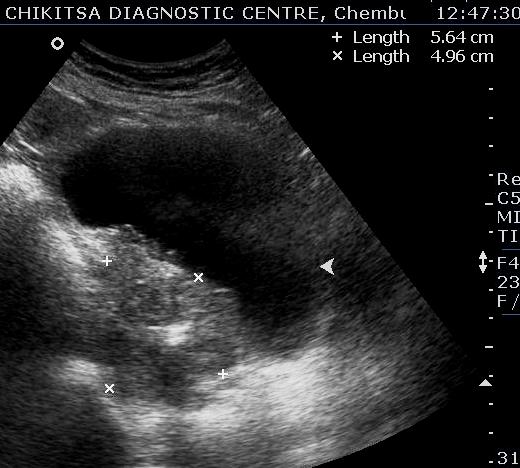

July-Aug 2012 :

Lesion in the wall of the urinary bladder has increased in size. Calcific areas are noted. Urinary bladder malignancy ( confirmed by histopathology), possibly following schistosomiasis.